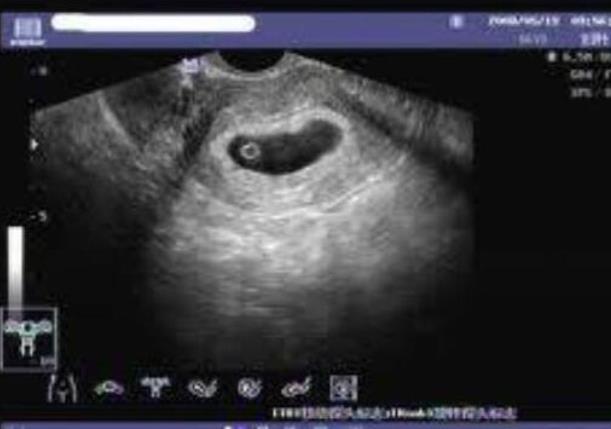

移植后14天,医生会安排试管病人医院抽血查hcg做孕检。如果验孕成功,就要做一个渐进式的检查,比如b超检查等。,可能要几十上百元。